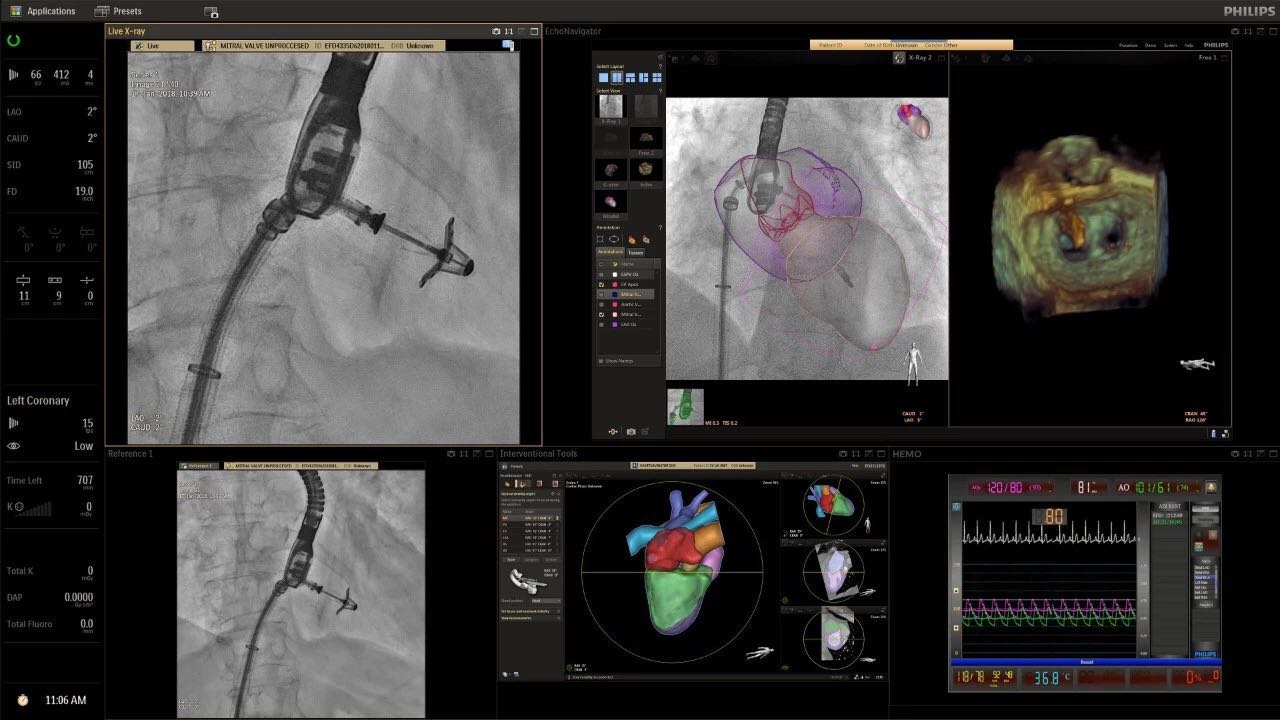

在日益復(fù)雜的干預(yù)期間,臨床醫(yī)生需要快速、輕松地可視化關(guān)鍵解剖結(jié)構(gòu)并確定手術(shù)過程中患者的變化。2019年1月17日,飛利浦宣布推出采用FlexArm的Azurion 7 C20,旨在提高圖像引導(dǎo)程序的定位靈活性。

帶有FlexArm的Azurion 7 C20 包含一系列創(chuàng)新技術(shù),使臨床醫(yī)生可以更輕松地在整個(gè)患者身上進(jìn)行二維和三維成像。當(dāng)臨床醫(yī)生移動系統(tǒng)時(shí),圖像光束自動保持與患者的對準(zhǔn),允許更一致的可視化并使他們能夠?qū)⒆⒁饬性谥委熒稀?/span>

“憑借FlexArm,飛利浦的工程師已經(jīng)克服了幾乎不可能的幾何和機(jī)械障礙,使臨床醫(yī)生能夠在圖像引導(dǎo)治療方面實(shí)現(xiàn)臨床卓越,”邁阿密心臟與血管研究所創(chuàng)始人兼首席醫(yī)療主管Barry T. Katzen博士說?!癋lexArm使我們能夠大大優(yōu)化患者周圍的程序,我們可以最佳地了解患者體內(nèi)的情況,而不會妨礙所有在桌面上工作的臨床醫(yī)生。結(jié)果是一項(xiàng)不僅具有臨床重要性,而且使用起來非常簡單直觀的創(chuàng)新。這是復(fù)雜手術(shù)過程中的一個(gè)關(guān)鍵因素?!?

(FlexArm C型臂可以沿著工作臺的兩側(cè)提供偏心成像。這允許醫(yī)生在左臂或右臂上進(jìn)行徑向進(jìn)入病例,完全或部分伸展,而無需移動患者或樞轉(zhuǎn)桌子。X射線束與手臂保持對齊,以促進(jìn)其整個(gè)長度的平滑導(dǎo)航,而無需進(jìn)行持續(xù)調(diào)整。)

飛利浦表示,采用FlexArm設(shè)計(jì)的Azurion 7 C20可提供卓越的靈活性和直觀的控制。該系統(tǒng)由智能運(yùn)動引擎驅(qū)動,可在八個(gè)不同的軸上移動,所有這些軸均由其單個(gè)“Axsys”控制器控制。臨床醫(yī)生的模擬測試表明,該系統(tǒng)有可能顯著減少患者,工作人員和設(shè)備的重新定位,從而改善微創(chuàng)手術(shù)的可及性,包括通過患者手腕進(jìn)入身體的手術(shù)(橈動脈入路),并降低患者的風(fēng)險(xiǎn)。無意中拔出電線和管子,以及節(jié)省大量時(shí)間。該系統(tǒng)非常適合混合手術(shù)室(OR),可滿足一個(gè)房間內(nèi)的多種專業(yè)需求,例如手術(shù)和血管內(nèi)手術(shù)的組合。

FlexArm在不少于8軸的情況下旋轉(zhuǎn),從而創(chuàng)建幾乎無限的靈活性來執(zhí)行成像,從頭部到腳部在左側(cè)和右側(cè)進(jìn)行2D和3D可視化。圖像光束保持與患者對齊,允許在旋轉(zhuǎn)或角度期間更好地可視化解剖結(jié)構(gòu)。使用Axsys運(yùn)動控制系統(tǒng)輕松操作支架。